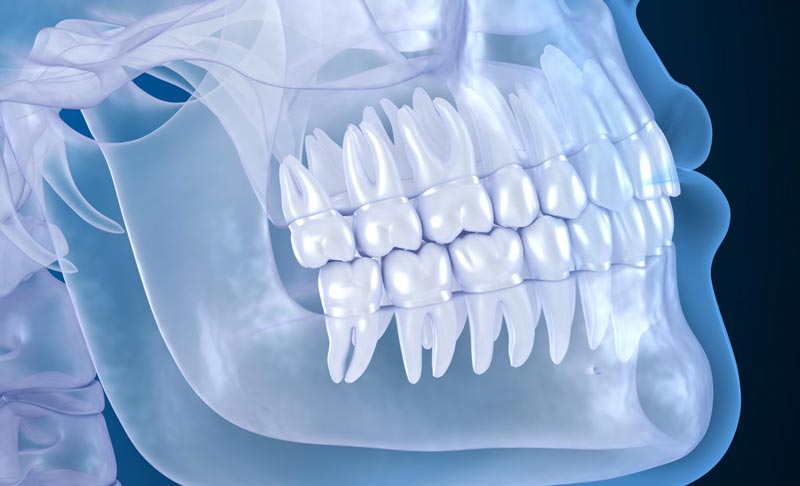

Cone beam computed tomography (CBCT) is an imaging technique that makes use of a rotating X-ray tube device. Similar to a CT scanner. However, the machine can produce very detailed images of that region of the mouth and jaw.

This scan gives a view of the teeth, jawbone, and adjacent structures inside the oral cavity where patients are being scanned. In addition, it allows dentists to evaluate not only the height and orientation of teeth but also the bones with high precision.

CBCT scans are valuable for determining tooth position, identifying any issues, moulding and implanting dental prosthetics, and evaluating the structure of the jaw and facial bones effectively. In times CBCT scans have gained acceptance among specialized dental professionals emerging as a primary standard in both orthodontic practices and general dentistry. Our dentist in Langley at Langley Dental Group utilizes advanced Dental CBCT Scans to provide precise and comprehensive diagnostics for effective treatment planning.